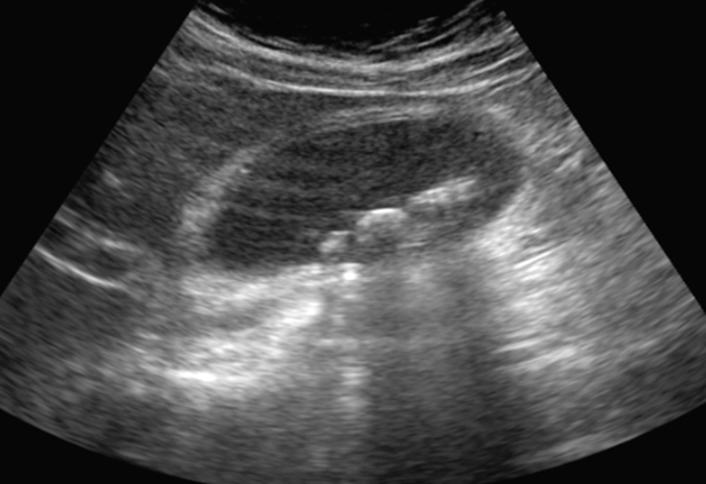

Ultrasound Pelvis is shown in the image below:

What is your most likely diagnosis?

What is your full management plan?

Ovarian Torsion